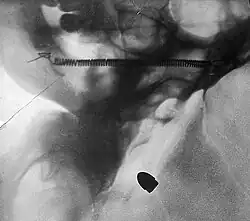

A bullet in the base of a brain, radiograph by Arthur Schuster, c. 1895 -

Radiograph of a pantomime artist's foot, revealing a needle by one of the toes, c. 1895 -